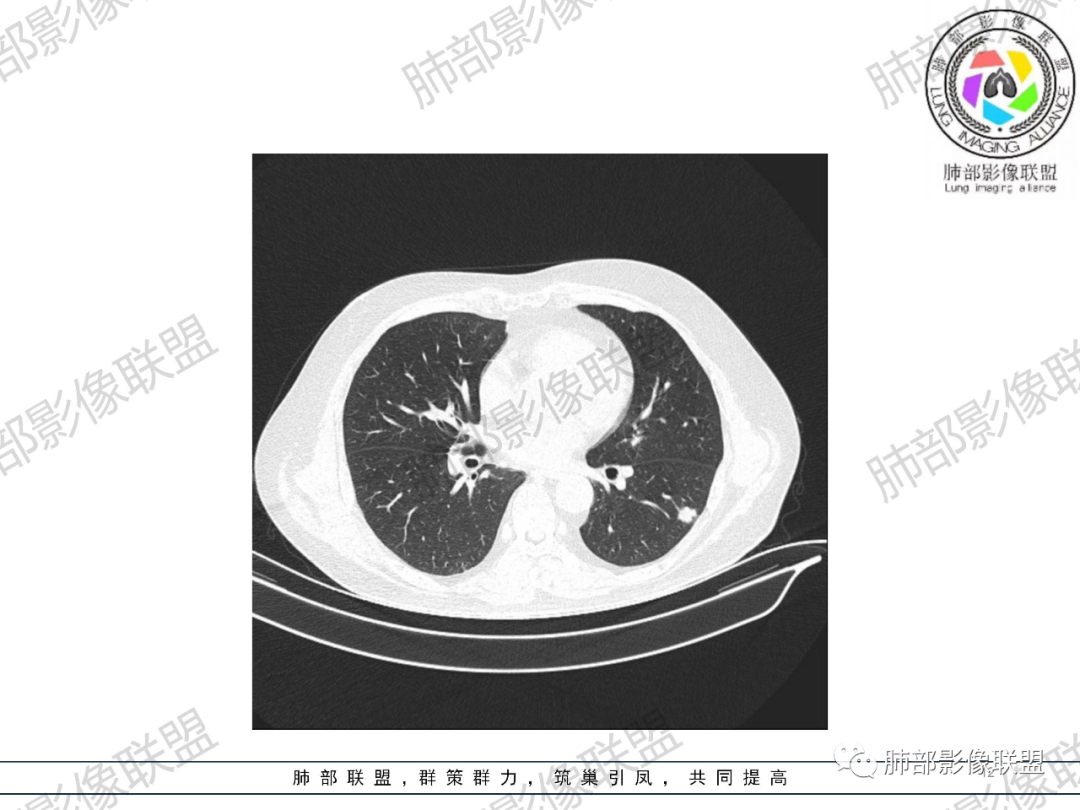

2.19年4月影像显示左肺下叶背段胸膜下浅淡小结节影,边界可分辨,密度不均有堆积感。

19年7月左肺下叶结节影轻度增大,渐至密实,小结节堆积感明显,边缘呈浅分叶。未见支气管进出。

20年8月左肺下叶结节影增大,密度增高,未见钙化及液化空洞。边缘浅分叶并见毛刺,胸膜牵拉线收缩乏力,未形成典型胸膜凹陷。可见供血血管,脐凹征不明显。未见典型卫星病灶。